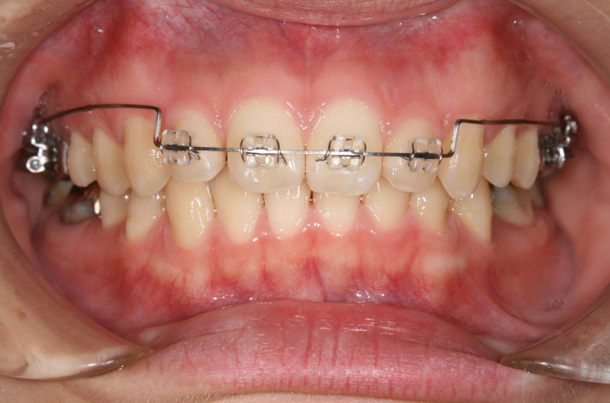

症例1

主訴:上の前歯がガタガタしている

年齢:9歳

診断:上顎前歯の叢生

装置:ブラケット装置(上顎の4前歯と第一大臼歯のみ)

治療期間:6ヶ月(来院回数7回)

抜歯:なし

費用:125,000円+税

矯正前

矯正後